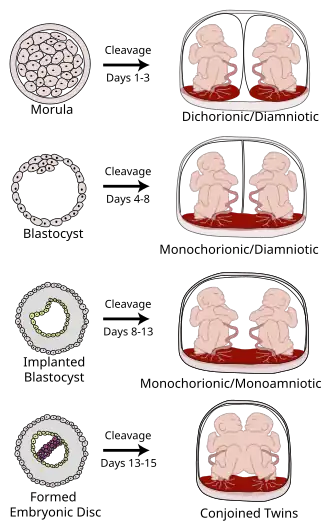

Various types of chorionicity and amniosity (how the fetus' sac looks) in monozygotic (identical) twins as a result of when the fertilized egg divides

The degree of separation of the twins in utero depends on if and when they split into two zygotes. Dizygotic twins were always two zygotes. Monozygotic twins split into two zygotes at some time very early in the pregnancy. The timing of this separation determines the chorionicity (the number of placentae) and amniocity (the number of sacs) of the pregnancy. Dichorionic twins either never divided (i.e.: were dizygotic) or they divided within the first four days. Monoamnionic twins divide after the first week.

In very rare cases, twins become conjoined twins. Non-conjoined monozygotic twins form up to day 14 of embryonic development, but when twinning occurs after 14 days, the twins will likely be conjoined.[45] Furthermore, there can be various degrees of shared environment of twins in the womb, potentially leading to pregnancy complications.

It is a common misconception that two placentas automatically implies dizygotic twins, but if monozygotic twins separate early enough, the arrangement of sacs and placentas in utero is in fact indistinguishable from that of dizygotic twins.

Type Description Day

Dichorionic–diamniotic Normally, twins have two separate (di- being a numerical prefix for two) chorions and amniotic sacs, termed dichorionic–diamniotic or DiDi. It occurs in almost all cases of dizygotic twins (except in very rare cases of fusion between their blastocysts[46]) and in 18–36%[47] (or around 25%[46]) of monozygotic (identical) twins.

DiDi twins have the lowest mortality risk at about nine percent, although that is still significantly higher than that of singletons.[48]

Dichorionic–diamniotic twins form when splitting takes place by the third day after fertilisation.[46]

Monochorionic–diamniotic Monochorionic twins share the same placenta.

Monochorionic twins generally have two amniotic sacs (called monochorionic–diamniotic MoDi), which occurs in 60–70% of the pregnancies with monozygotic twins,[47] and in 0.3% of all pregnancies.[49] Monochorionic–diamniotic twins are almost always monozygotic, with a few exceptions where the blastocysts have fused.[46]

Monochorionic twins share the same placenta, and thus have a risk of twin-to-twin transfusion syndrome.

Days 4–8

Monochorionic–monoamniotic Monochorionic twins share the same amnion in 1–2% of monozygotic twin pregnancies.[47]

Monoamniotic twins are always monozygotic.[50]

The survival rate for monoamniotic twins is somewhere between 50%[50] and 60%.[51]

Monoamniotic twins, as with diamniotic monochorionic twins, have a risk of twin-to-twin transfusion syndrome. Also, the two umbilical cords have an increased chance of being tangled around the babies. Because of this, there is an increased chance that the newborns may be miscarried or develop cerebral palsy due to lack of oxygen.

Monoamniotic twins occur when the split takes place after the ninth day after fertilization.[46]

Conjoined twins

When the division of the developing zygote into two embryos occurs, 99% of the time it is within eight days of fertilization.

Mortality is highest for conjoined twins due to the many complications resulting from shared organs.

If the division of the zygote occurs later than the 12 days then conjoined twins are usually the result.